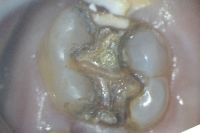

いわゆる大人のむし歯(つめものの下のむし歯)です。

みたところ問題はないようですが、水はしみて痛みのある状態です。

健康な歯質をけずらないように、金属のみを慎重に外していきます。

はずしてみると中はこんな状態でした。金属とのスキマからむし歯が中にひろがっていました。

特に歯ぐきがわのスキマからのむし歯が大きくなっていました。

むし歯になってしまった歯質のみを慎重に取り除きます。

このようにマイクロスコープを用いると、健康な歯質を可能な限り温存できるので、歯にとっては最小限の治療ですみます。